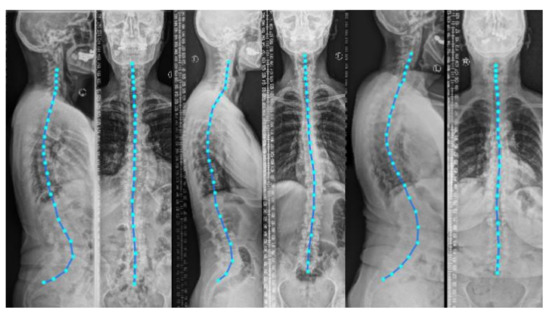

We validate TransVert+ on clinical, standing radiographs (pairs of lateral and anterior-posterior projections) acquired from 30 patients. Before deploying our TransVert+ model on the clinical radiographs, we resampled all radiographs to 1 mm resolution.

Image acquisition parameters such as the source-to-detector and source-to-object distances were similar to those used for DRR generation. We employed [37,38] to automatically generate the vertebral annotations on both views.

3.1. 2D-to-3D Translation in Clinical Radiographs

Figure 10 depicts the results of deploying TransVert+ for reconstructing the 3D, patient-specific posture of the upright standing spine. As stated, there is no 3D ground truth spinal model for the clinical radiographs. Observe the matched reconstruction of the 3D spine posture to the spinal posture in radiographs.

Figure 10. Full 3D spine models: 3D patient-specific spine models constructed from real clinical radiographs. Each sagittal and coronal view radiograph pair is from a different patient.